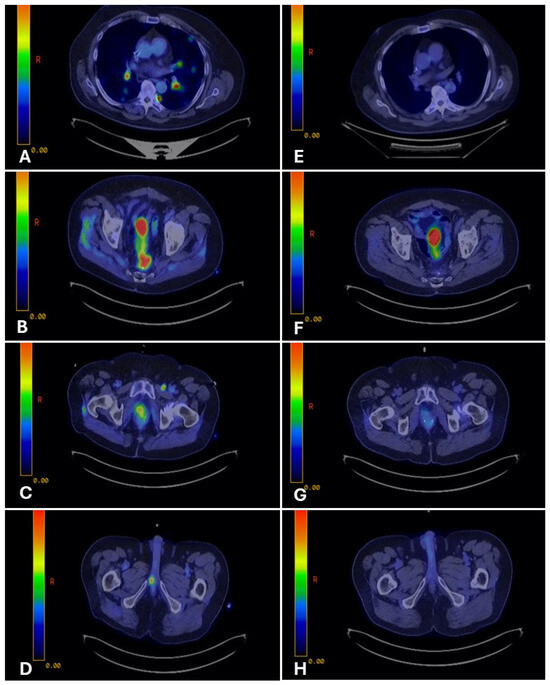

A 61-year-old never-smoking male with no significant past medical history presented in November 2023 with right-sided tongue and ear pain. CT imaging revealed levels II and III cervical lymphadenopathy. Ultrasound-guided fine-needle aspiration of a right cervical lymph node showed metastatic adenocarcinoma with mucinous features. Immunohistochemistry demonstrated diffuse strong nuclear positivity for CDX2 (Figure 1B,E) and CK20, focal positivity for CK7, and negativity for ER, HER2, SATB2, SOX10, and TTF-1. A staging PET-CT revealed FDG-avid right cervical lymphadenopathy and mild asymmetric uptake in the right palatine tonsillar region, with no evidence of distant metastasis (Figure 3A).

Figure 3.

PET-CT imaging before and after fluoropyrimidine-based therapy in Case 2. Legend: Representative PET-CT images demonstrating disease before therapy and response after fluoropyrimidine-based treatment. Pre-treatment (A): FDG-avid right cervical lymphadenopathy and mild asymmetric uptake in the right palatine tonsillar region. Post-treatment (B): Restaging PET-CT demonstrates resolution of metabolic activity, with decreased enhancement at the primary site and marked reduction in cervical nodal size, consistent with a complete metabolic response.

The patient then transitioned to concurrent chemoradiation, with FOLFOX administered at radiosensitizing doses. Three months after completion of chemoradiation, restaging with PET-CT demonstrated no evidence of active disease, with decreased enhancement at the primary site and reduction in nodal size (Figure 3B). Serial MRIs over subsequent months showed stable post-treatment changes without progression. The patient has now been without evidence of active disease for two years, maintaining good functional status with preserved speech and swallowing.